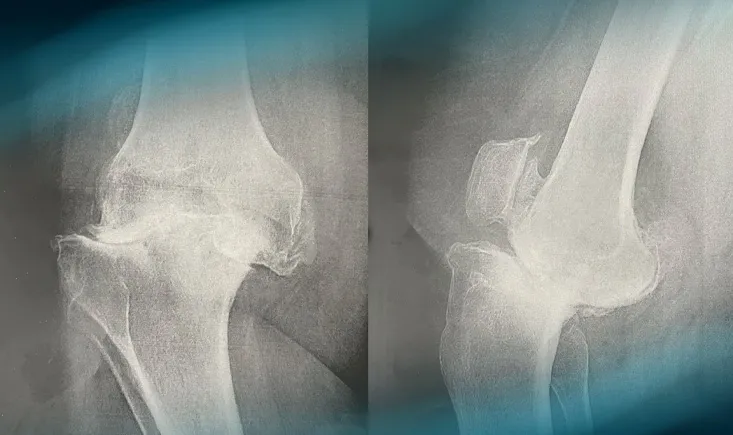

Frane Bukvić presents the case of a 34-year-old orthopaedic surgeon​ suffering from a symptomatic chondral ‘ki…